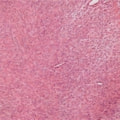

症例:肝臓の結節性過形成 犬、11歳、去勢雄

持続的な肝酵素の上昇が認められるとのことで来院。肝保護剤等による内科療法および食事療法で肝酵素の改善が得られず、腹部の超音波検査を実施、肝臓実質に腫瘤性病変の形成を認めた。病変部の拡がりおよび転移の有無の確認のため、CT検査を実施。その結果、肝臓の内側左葉に直径7cm×6cm×5cmの腫瘤性病変を認めた。病変は単一であり、肺等への転移所見が無いことから、摘出手術を実施、病理組織検査にて「結節性過形成」と診断された。

CT写真

結節性過形成は、高齢の犬において多く認められる良性の非腫瘍性病変である。通常は、3cm程度までの小型の腫瘤であり、血液検査上の異常を示すことはほとんどないと言われている。肝細胞癌等の悪性腫瘍との鑑別は、超音波検査やCT検査、細胞診検査等だけでは困難である。多くの場合、確定診断のためには、腫瘤の摘出手術を実施し、病理組織検査を行うことが必要となる。本症例のように、肝臓の腫瘤が3cm以上の大型である場合は特に、悪性腫瘍の可能性も考慮し、摘出を検討して検査を進める必要がある。

本症例は、悪性腫瘍ではなく結節性過形成との診断であるため、今回の摘出により予後は良好であると考えられる。